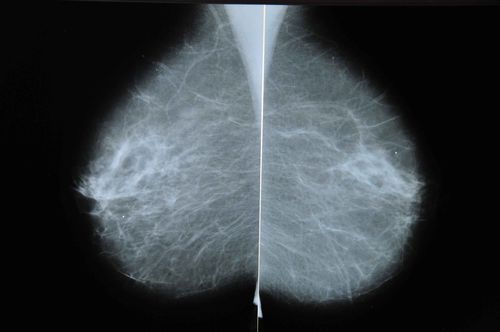

After the ultrasound, Quasha's radiologist was concerned. She told Quasha she considered the lump she had felt in her breast to be of little significance, but the lymph nodes that showed up as white blobs on her mammogram were another matter.